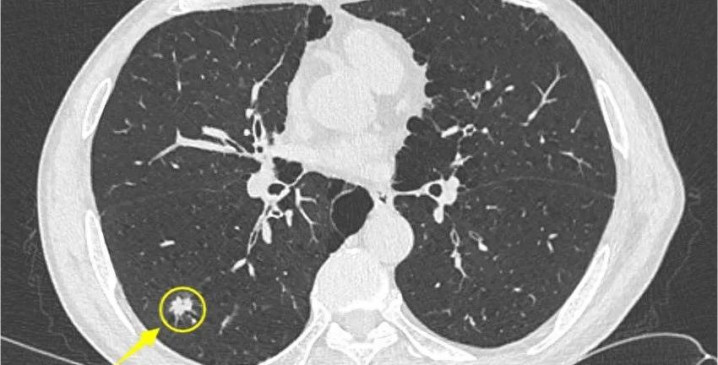

昨年接诊的45岁的刘女士,因体检发现右肺一个6mm的磨玻璃结节,整天忧心忡忡。她自述平时爱生闷气,两胁胀痛,月事前乳房胀痛,嗓子总合计有痰。不雅其舌象,舌暗红,苔薄黄,边有瘀点,这是典型的肝郁气滞、痰瘀互结证。春季肝气应时,她这种体质最容易加剧。

她坚合手防备了三个月金年会体育,本领谄谀春季食疗,自述胸闷、胁痛默契改善。后复查CT透露:6mm磨玻璃结节已奢靡祛除!